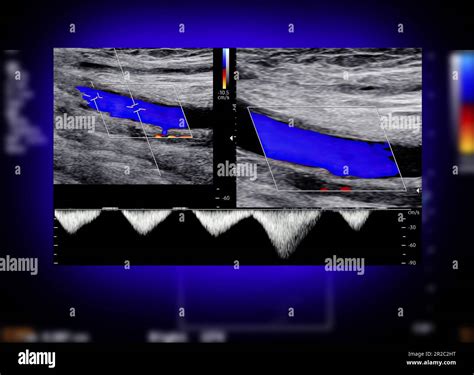

One such advancement is the use of Doppler ultrasound, which not only provides visual images but also measures the speed and direction of blood flow. This information can help healthcare providers assess the severity of blockages more accurately.

Carotid Artery Ultrasound